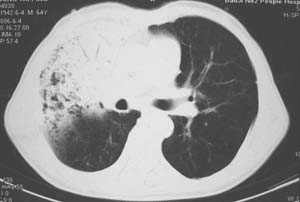

右肺上叶大片片状、网格状及索条致密影,前半部密实向后逐渐疏松,其内参杂斑点状小结节,密度不均匀,内见含气支气管像,纵隔内见肿大淋巴结,其他肺呈弥漫性小叶中心性性肺气肿改变,结合男 64  咳血,咳痰,发热3天,血象1.2万。考虑:1 慢性支气管炎、肺气肿合并右上肺感染。2 不除外结核合并感染的可能。

影像表现:肺窗示右肺上中叶均可见小片、条索状、小结状密度增高影,可见支气管充气相,小叶间隔增厚,支气管通畅,余肺未见明显异常。纵隔窗示4r可见小淋巴结融合,无明显肿大,右侧示少量胸腔积液。

右侧胸阔塌陷,纵隔右移。右上肺大片状高密度影,沿支气管血管束走行,内见点状钙化;支气管充气征阳性,支气管呈柱状扩张;胸膜下小叶间隔增厚;右侧后胸壁内侧见带状水样密度影;纵隔淋巴结增大。

影像学表现:右肺上叶大片状、网格状及索条致密影,前半部密实向后逐渐疏松,其内参杂斑点状小结节,密度不均匀,内见含气支气管像,纵隔内见肿大淋巴结.

右肺上叶见片状,网格状及索条样致密影,内见支气管气相,纵隔内见肿大淋巴结,同侧胸腔内少量液性密度影,余肺呈肺气肿改变,临床:男,64岁,咳血,咳痰,发热3天,wbc---1.2万